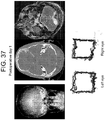

- the second patient was a 56 year old male who presented with a lung mass and headaches. He did not have papilledema on clinical examination. MRI revealed a large intraxial mass near the cerebellopontine angle, but interestingly, pushing the left side of brainstem up against the clivus rather than the right. Note that there was no transependymal flow on MRI to suggest hydrocephalus ( Figure 37 right). Eye tracking of the right eye demonstrated a box narrower than it was wide (increased aspect ratio) consistent with CN VI palsy. Postoperatively his aspect ratio returned to normal ( Figure 38 )

- Scatterplots of the entire time series were created by plotting the 100,000 (x,y) pairs representing the two orthogonal components of the instantaneous angle of pupil reflection over time to create 'box trajectories' that reflected the temporal nature of the pupillary movement.

- these figures look like boxes, reflecting the timing of the aperture as it moved around the screen ( Figure 20 ).